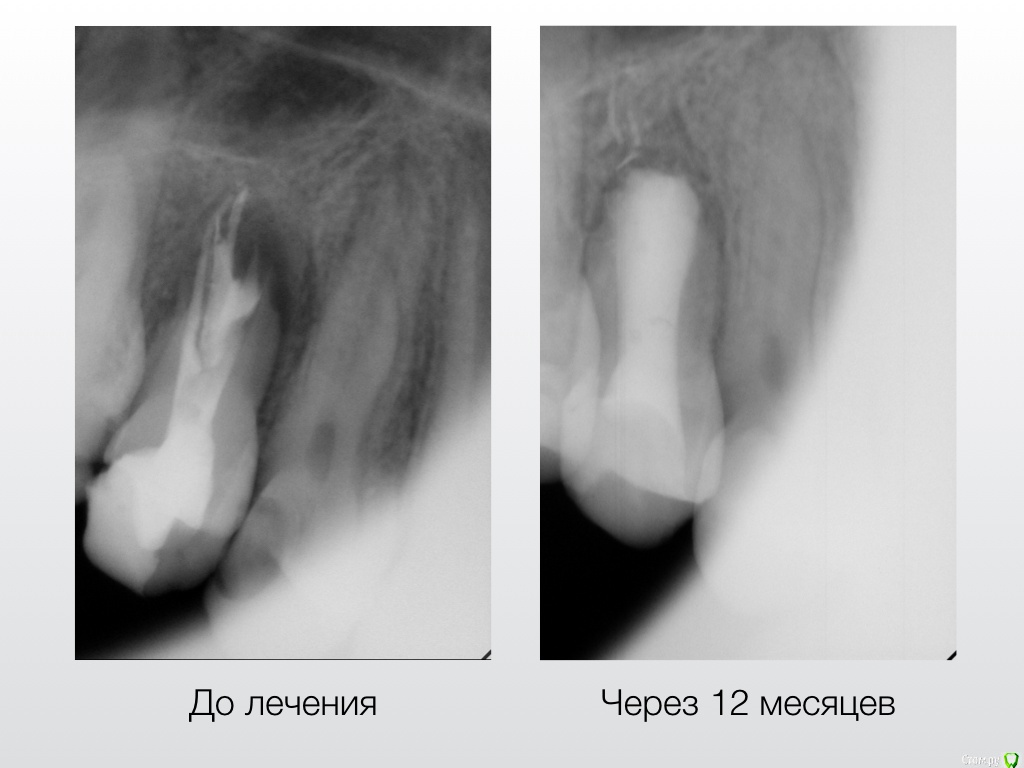

Гарриевич Опубликовано 2 августа, 2018 Автор Поделиться Опубликовано 2 августа, 2018 Вот вся история в картинках 13 Ссылка на комментарий

ger_berra Опубликовано 9 августа, 2018 Поделиться Опубликовано 9 августа, 2018 Вот вся история в картинкахF3CD8F8E-36A2-482B-BFD4-6A0883546283.jpeg2A06B29D-2BDF-4869-A8F8-E02567619146.jpeg47F31C36-F9FE-40C6-9236-3A6203A894B7.jpeg8459AB75-F819-4664-9906-DB4BDCE505D2.jpeg9937DA00-9922-402C-AA29-5DD806AA0714.jpeg37DDB315-6893-49F4-A949-06BC6B58F996.jpegОтличный результат! 1 Ссылка на комментарий

Гарриевич Опубликовано 15 сентября, 2019 Автор Поделиться Опубликовано 15 сентября, 2019 результат через 2,5 года 5 Ссылка на комментарий